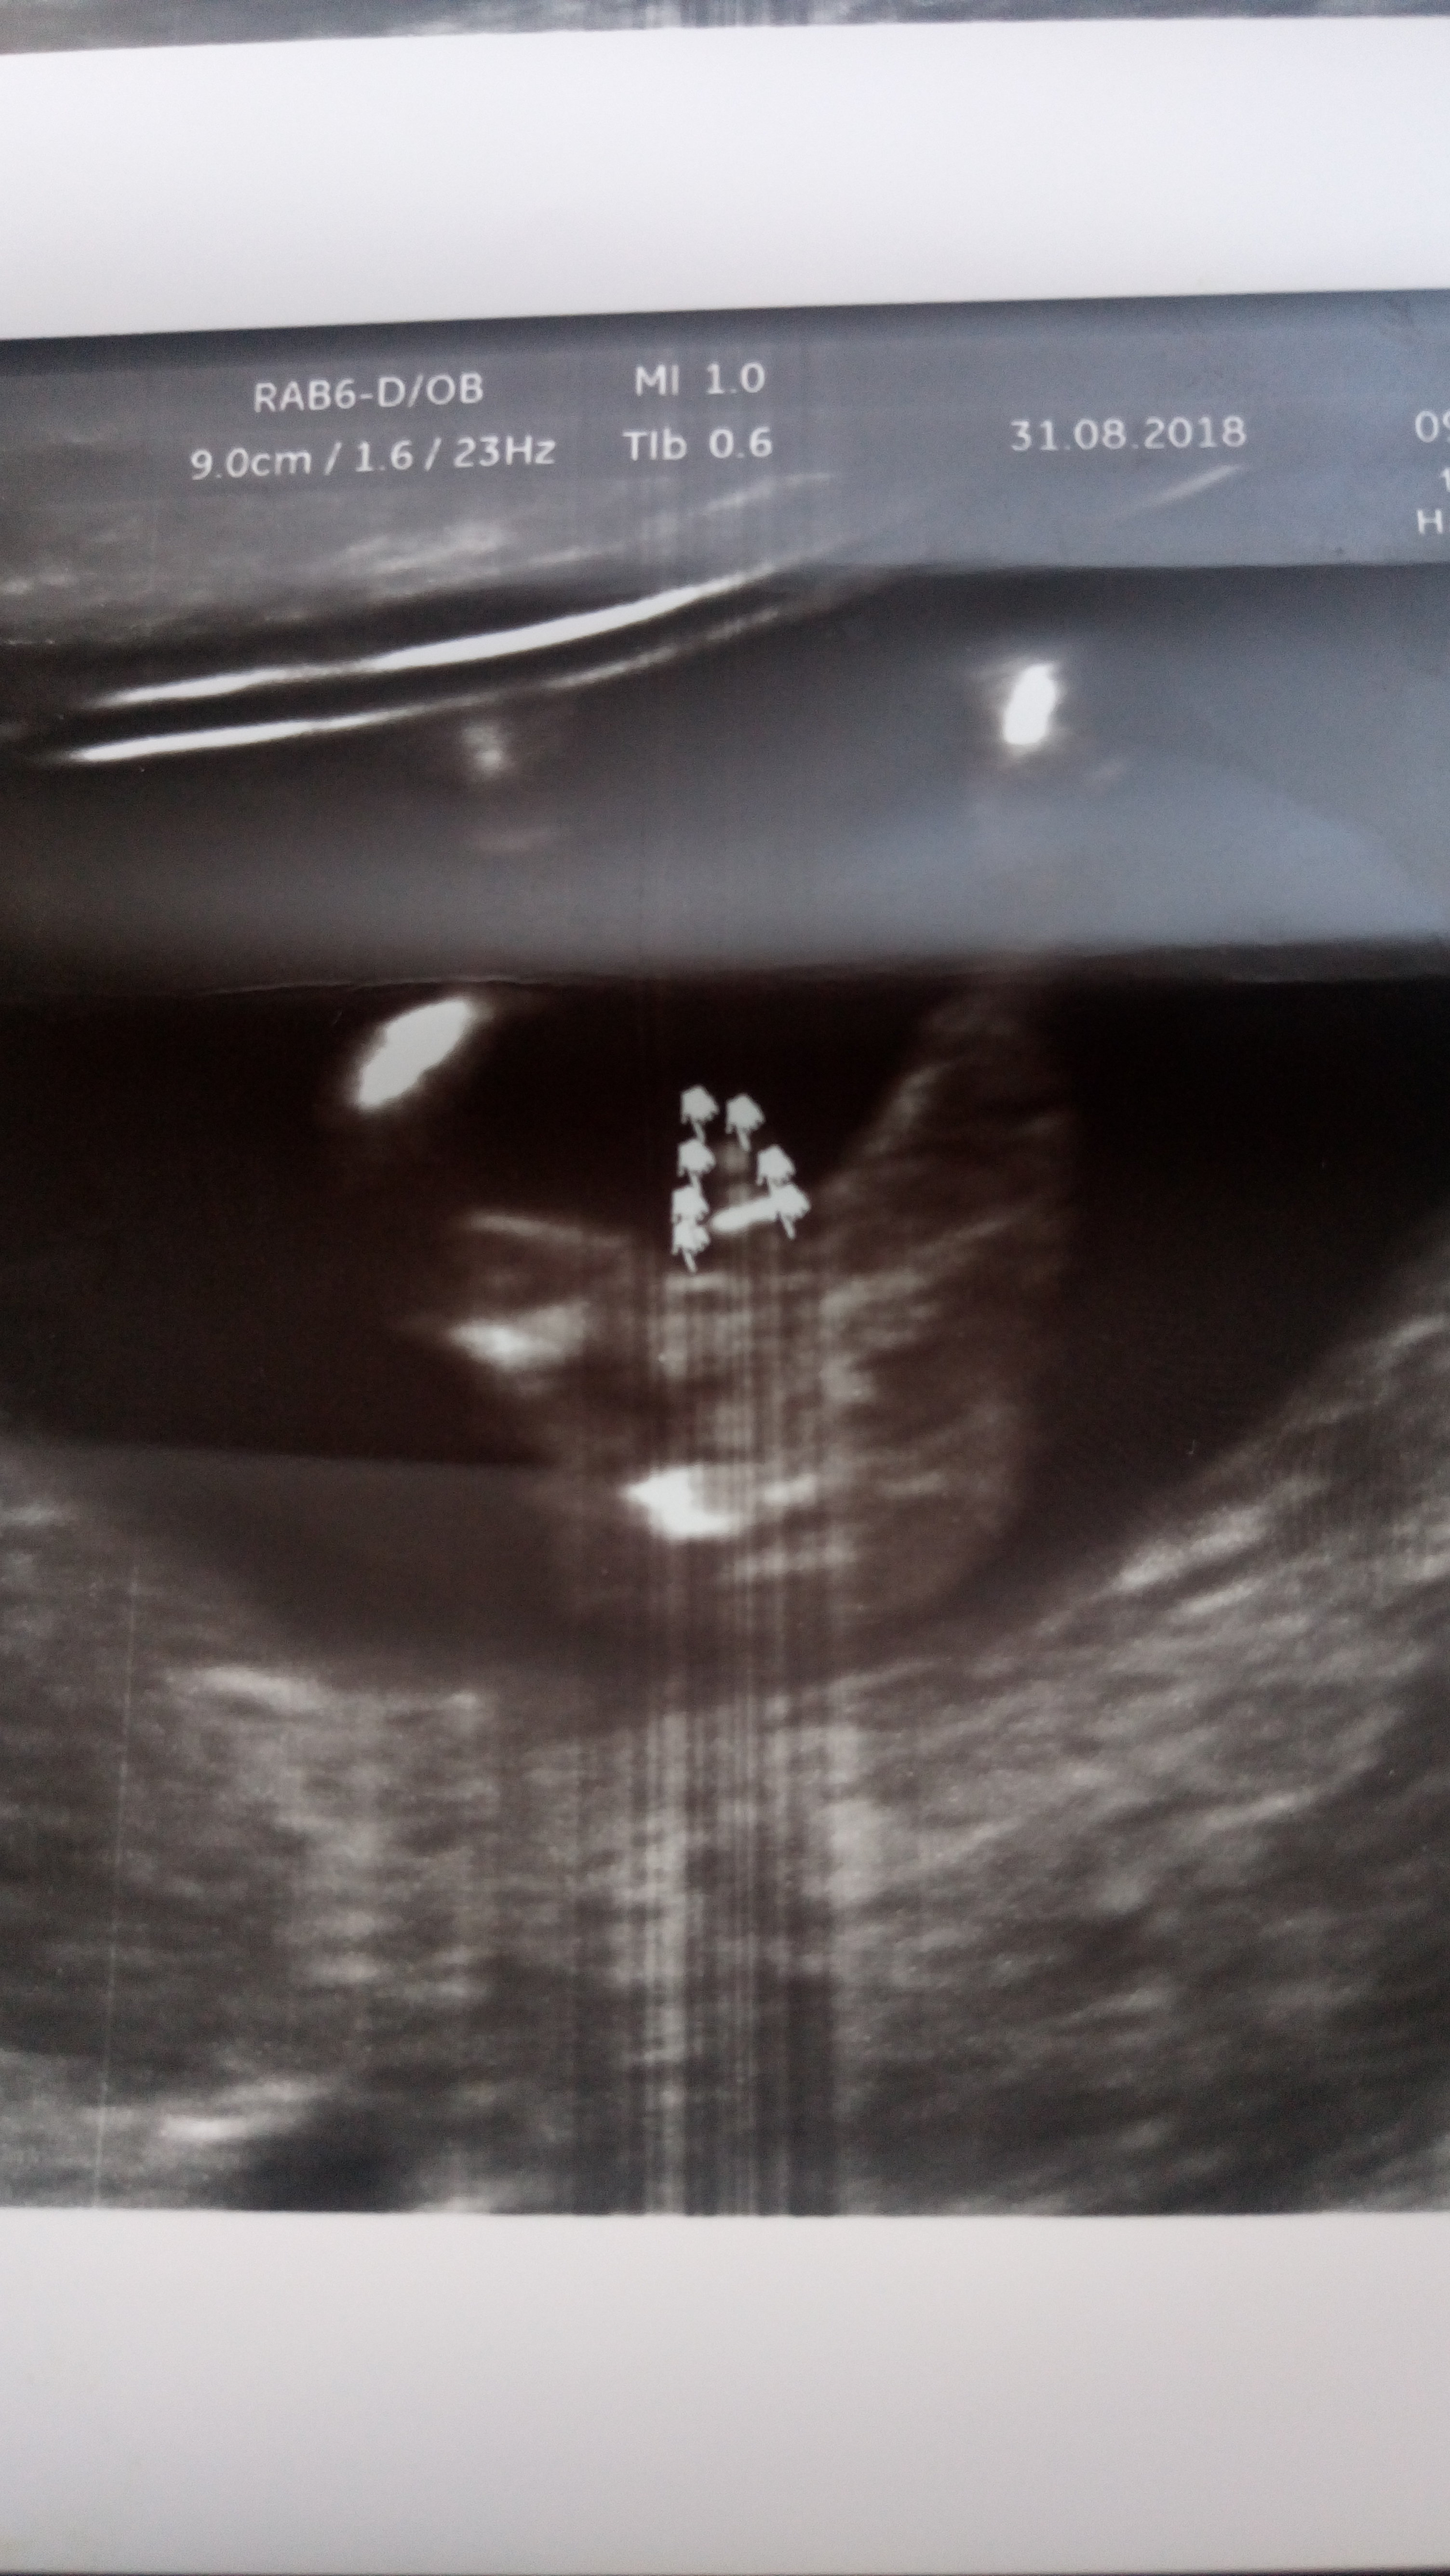

Witam Was. Może po tych zdjęciach da się odczytać płeć dzidziusia? Dodam że jest to 12+4 tc na prenatalnych Pani dr nie była pewna zajrzała tylko między nóżki na wyrostek nie patrzyła.

• DSC_2504.JPG

1,9 MB · Wyświetleń: 408

DSC_2503.JPG

• DSC_2505.JPG